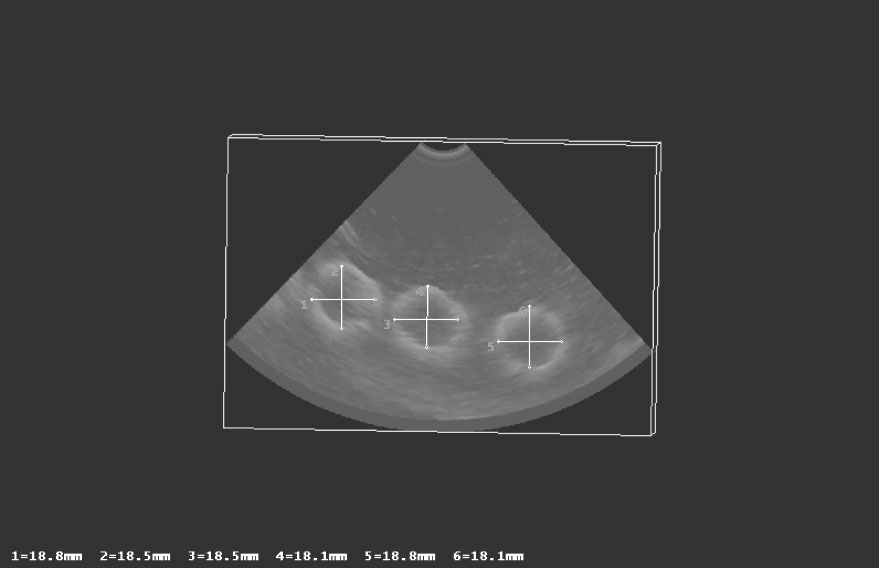

直線實驗說明本系統重建圖像在重建面長度測量上能夠準確得到物體的尺寸,但受限于系統所采用的B超系統和探頭,直線在整個三維體中并不是特別明顯,僅能在重建面上顯示直線的圖像,對于整個物體的變形程度沒有一個直觀的成像說明。為了進一步評估該系統三維成像效果的變形度,我們采用規則的圓形物體進行成像,這樣對于成像結果有一個直觀定量的評估。選用水來作為傳播介質,塑膠手套手指作為成像物體,該手指較為均勻,充滿水后,手指近似為一個圓柱形物體。手指直徑約為18.5 mm。在方形的盒子里注入水,塑膠手套內也裝入水并垂直放置在水盒中,實驗中探頭垂直放入水中,將手套的手指作為成像目標,用于支撐整體機械裝置的LCD支架固定在桌子的邊緣,如圖 7所示。

水對超聲波的吸收系數較小,1 MHz時僅為0.002 2 dB/cm,且成像體僅包括水和手套,因此得到的成像效果較為理想,如圖 8所示。能夠清楚地看到手套的手指形狀,邊緣非常清晰,且在重建面其形狀為規則的圓形。在重建面對手指直徑進行測量,六次測量結果分別為:18.8、18.5、18.5、18.1、18.1、18.8 mm,平均值約為18.5 mm(手指直徑真實值為18.5 mm)。